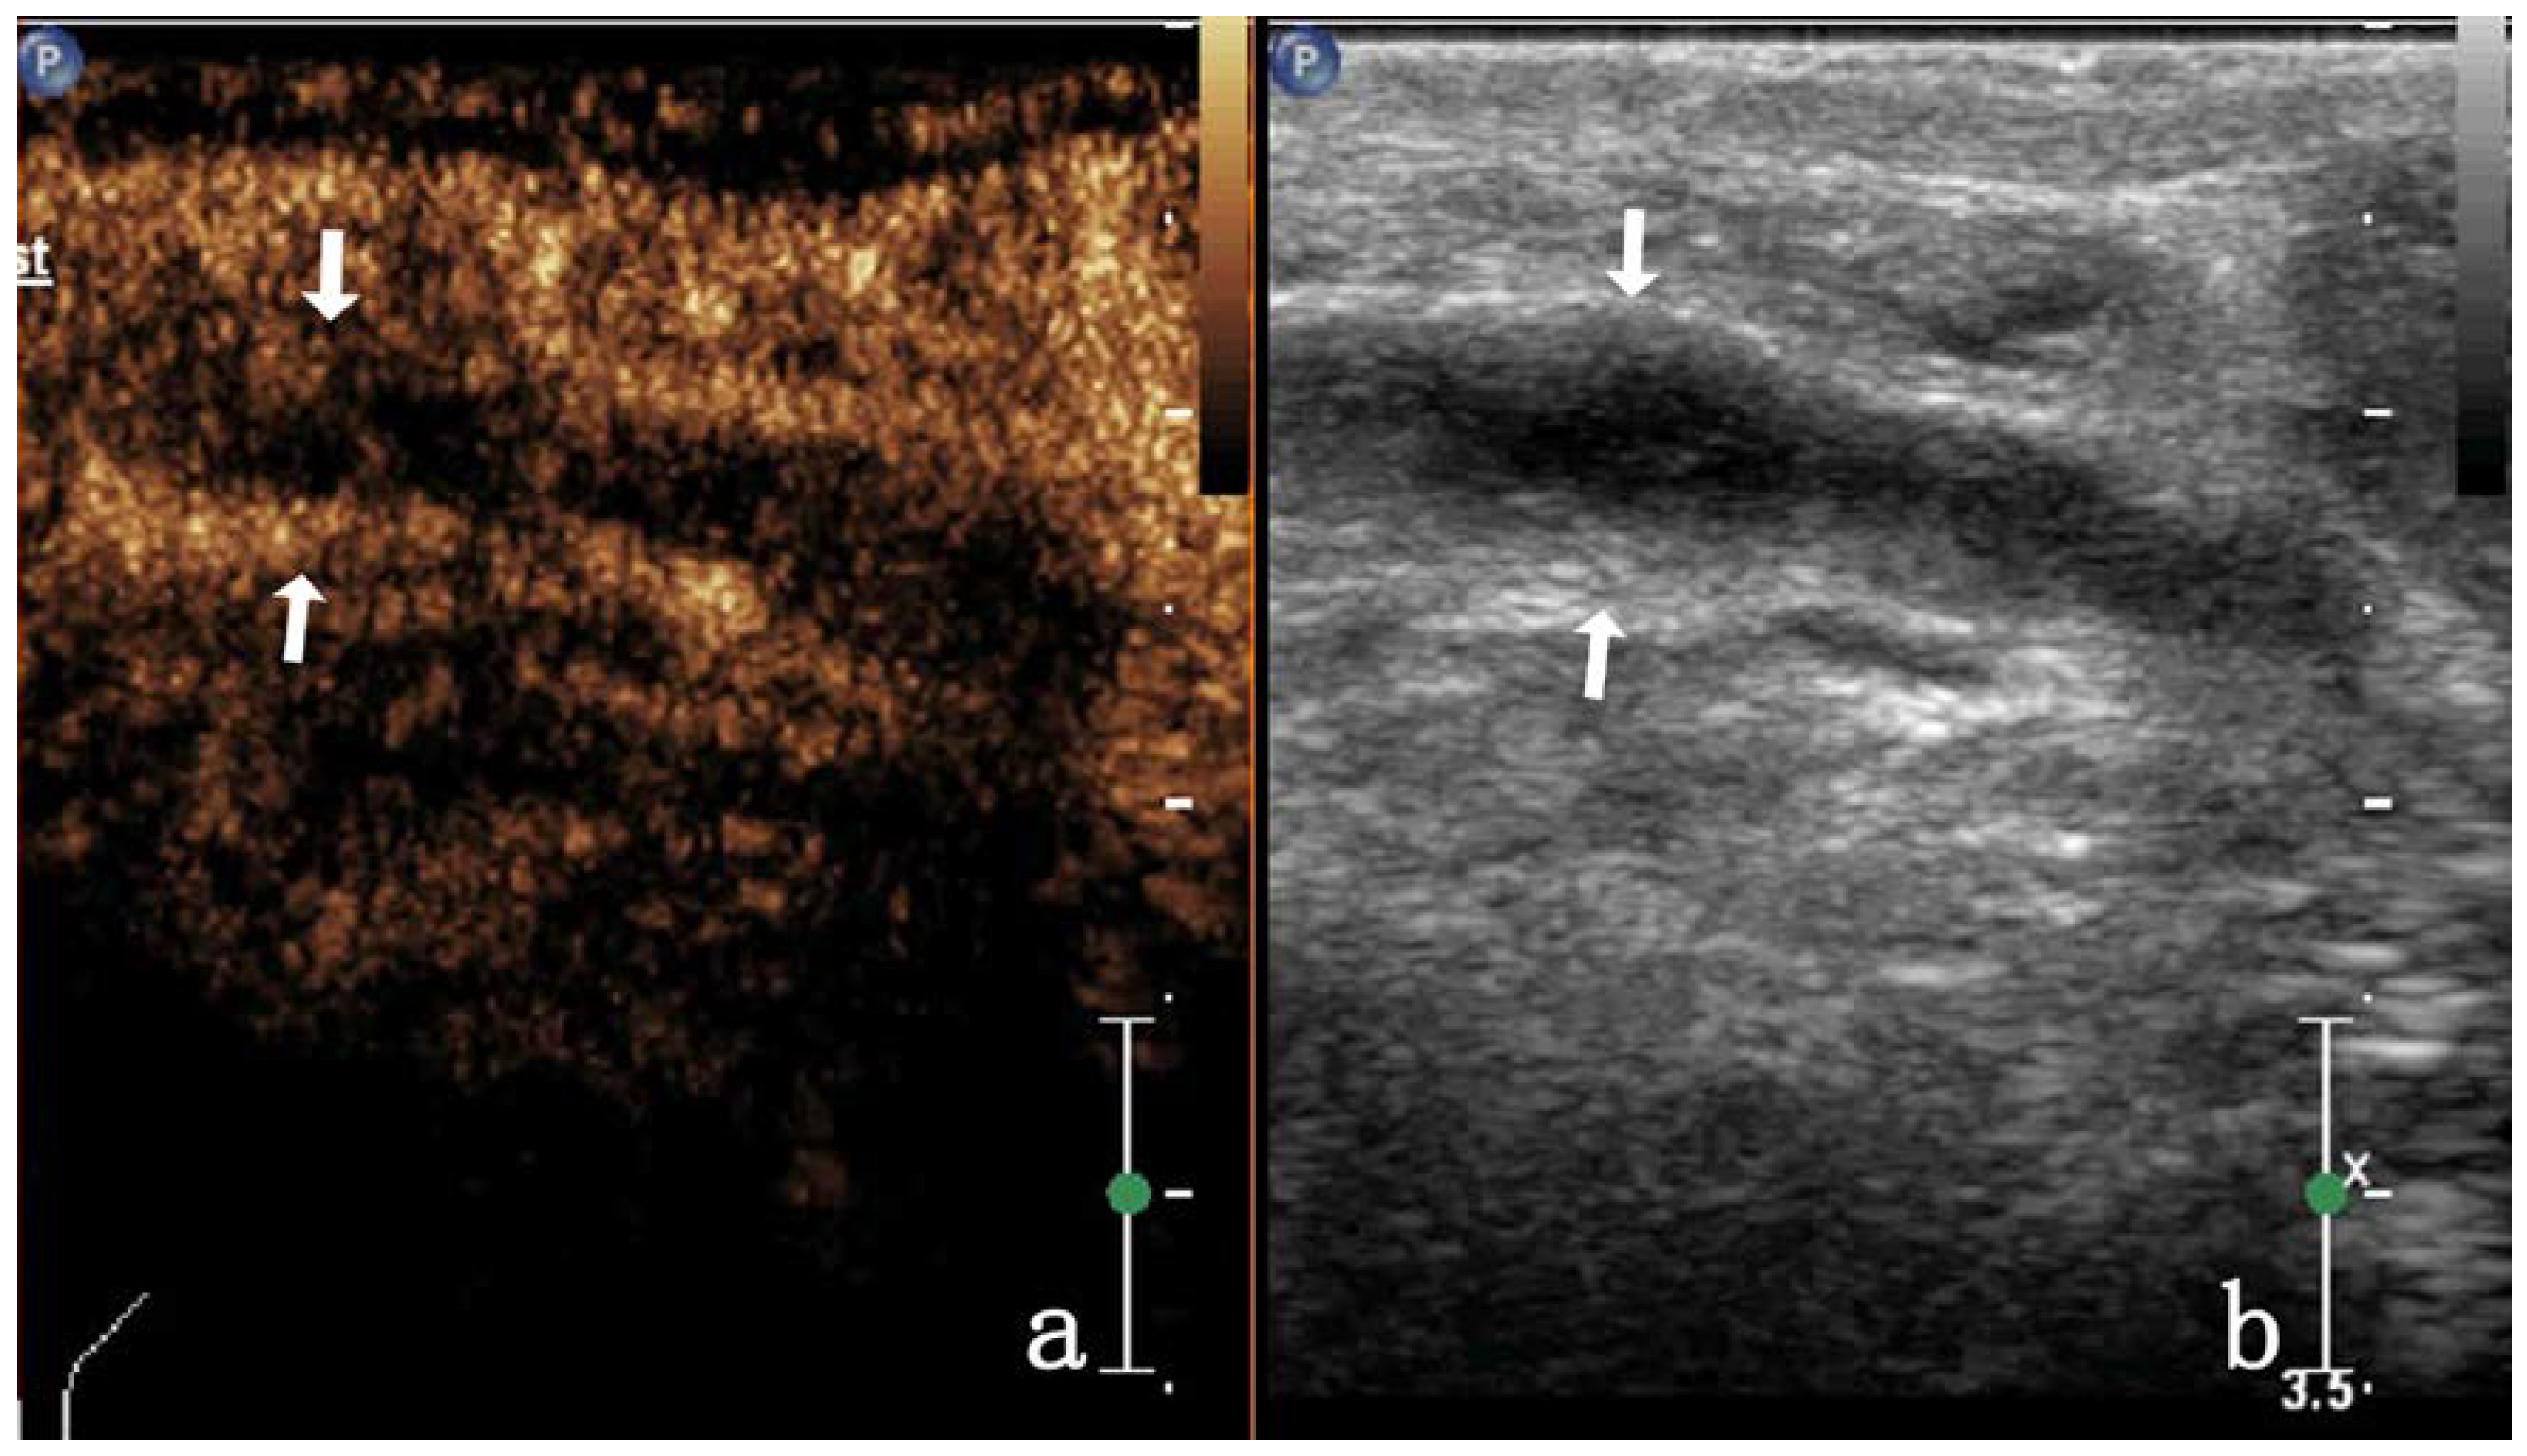

| Heterogeneous enhancement | septal enhancement | 4/17 (23.52%) | 0 | ||

| Annular enhancement | 4/17 (23.52%) | 5/28 (17.85%) | |||

| Nodule-in-nodule enhancement | 3/17 (17.64%) | 0 | |||

| non-enhancement | 3/17 (17.64%) | 0 | |||

| Low enhancement | 5/17 (29.41%) | 0 | |||

| Equal enhancement | 4/17 (23.52%) | 0 | |||

| Noncentripetal enhancement | 17/17 (100%) | 12/28 (42.85%) | |||